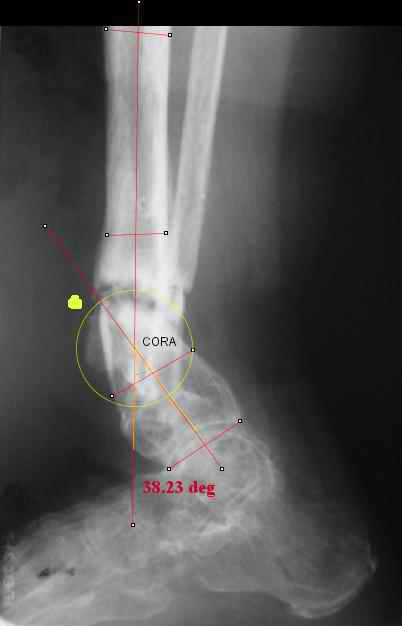

I played with your image using some orthopedic software we have been developing for digital

image analysis.

What you see marked up is the intercept of two mid-line tool centre lines, used to define the CORA. An angle tool gives the angular deformity and a circle tool is applied to show that a correction around the CORA through the old # will restore alignment without much translation.